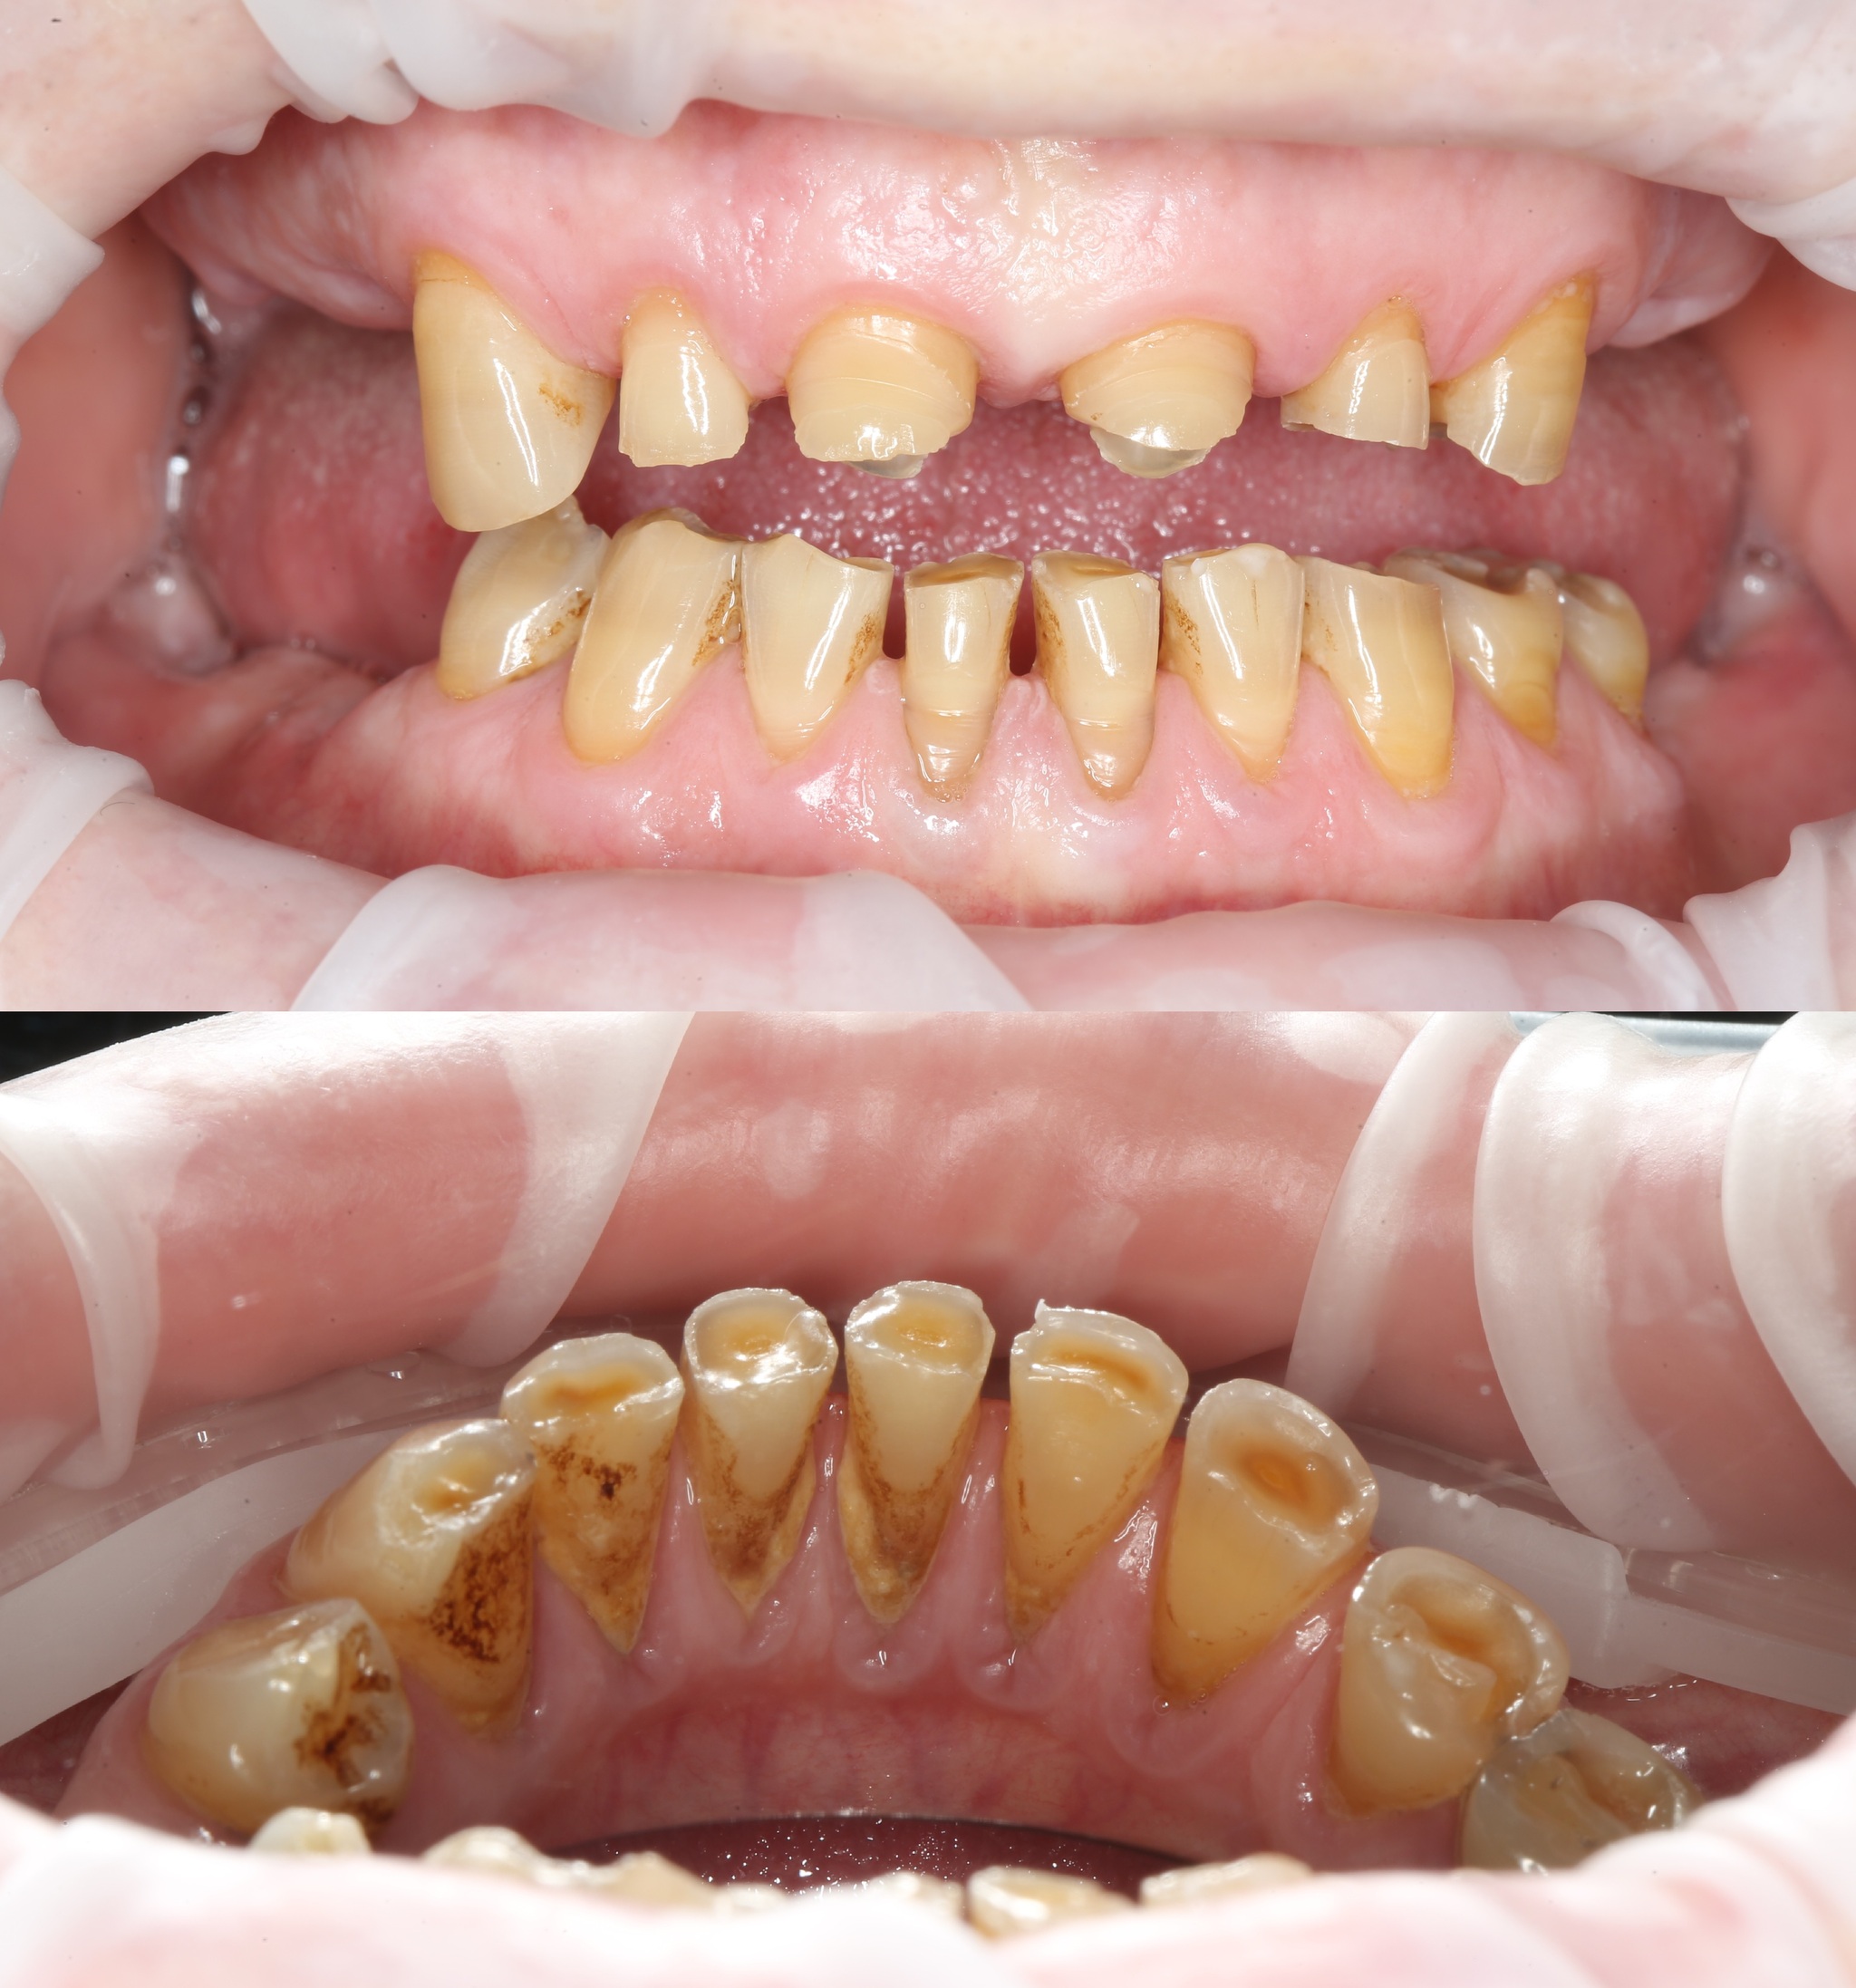

Первым делом была проведена профессиональная гигиена полости рта. Соглашусь, ее нужно было сделать еще до удаления зубов, но мы не укладывались в сроки.

Отмечается пигментированный зубной налет и отложения солей камней в области зубов на нижней челюсти с язычной стороны.

После чистки: